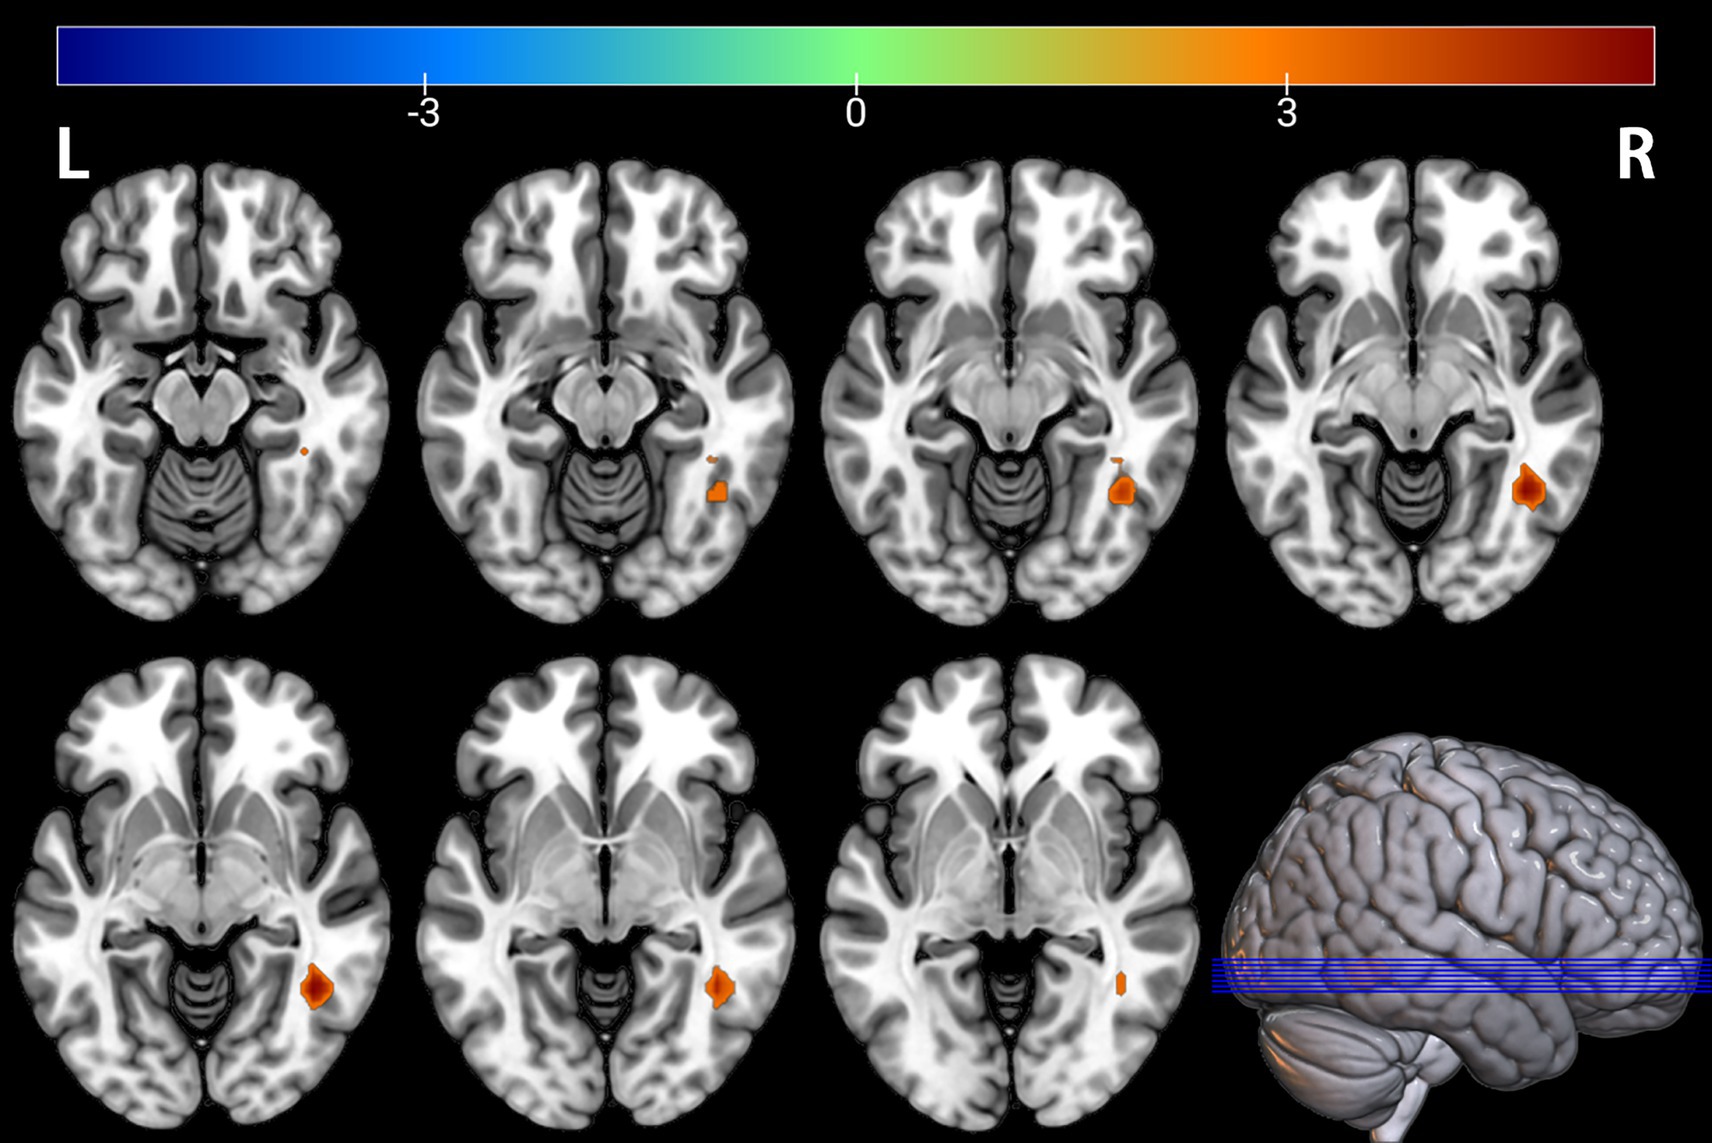

Figure 1

Brain regions with significantly increased ALFF in the PT group compared to the HC group. The results are displayed on a 3D brain template. Statistical significance was determined by a two-sample t-test, with voxel-wise FDR correction at p < 0.05. The color bar represents the T-value. Warm colors (red) indicate a significant increase in ALFF in the PT group. Significant clusters include the left fusiform gyrus (Fusiform_L), left middle temporal gyrus (Temporal_Mid_L), right middle occipital gyrus (Occipital_Mid_R), right middle temporal gyrus (Temporal_Mid_R), right calcarine cortex (Calcarine_R), right angular gyrus (Angular_R), and left calcarine cortex (Calcarine_L). R, right; L, left.

Comparison between the depressed PT group and the healthy HC group revealed differences in seven brain regions between the two groups (p < 0.05, FDR corrected, Table 2), with Fusiform_L, Temporal_Mid_L, Occipital_Mid_R, Temporal_Mid_R, Calcarine_R, Angular_R, and Calcarine_L increased (Figures 1, 2).

Table 2

| Fusiform_L (aal) | −30 | −66 | −9 | 3.7348 | 338 |

| Temporal_Mid_L (aal) | −54 | −30 | 3 | 4.125 | 176 |

| Occipital_Mid_R (aal) | 30 | −90 | 6 | 4.3296 | 195 |

| Temporal_Mid_R (aal) | 51 | −27 | −3 | 4.0037 | 114 |

| Calcarine_R (aal) | 21 | −66 | 12 | 3.1043 | 93 |

| Angular_R (aal) | 39 | −51 | 24 | 3.8749 | 81 |

| Calcarine_L (aal) | −15 | −72 | 15 | 3.415 | 91 |